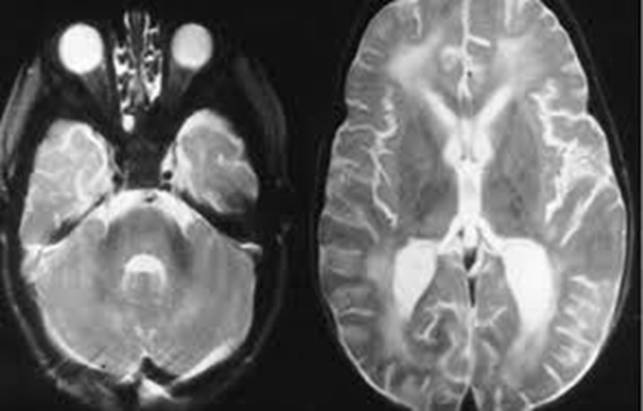

Liên quan đến các ca bệnh giun đầu gai này đã được ghi nhận một cách chi tiết, song cũng cần có luận bàn để trước khi đưa ra tiêu chuẩn chẩn đoán nhằm điều trị hiệu quả là quan trọng:

-Loạt bệnh nhân nhiễm G. spinigerum được báo cáo phần lớn bệnh nhân có liên quan đến yếu tố dịch tễ là du lịch hoặc thăm gia đình hoặc di dân vì lý do nào khác tại các vùng lưu hành và chế độ ăn ít nhiều có yếu tố dịch tễ bệnh ký sinh trùng này. Các hình thái du lịch quốc tế cho thấy rằng tình trạng này thường xảy ra cho các đối tượng đi du lịch và di dân đến các vùng bệnh lưu hành. Ngoài ra, sự phân bố về mặt địa lý của nhiễm bệnh cũng như gia tăng thói quen ăn uống của các du khách ở các vùng như thế đã góp phần vào tỷ lệ mắc bệnh giun đầu gai này;

-Trong số bệnh nhân mô tả ở trên, cho chúng ta thấy thời gian trung bình từ khi xuất hiện triệu chứng bệnh đầu tiên đến khi được chẩn đoán là 12 tháng (ít nhất là 3 tuần nhiều nhất là 5 năm), điều này phản ánh rằng cả tính tự nhiên xuất hiện triệu chứng từng đợt lẫn các chẩn đoán không rõ ràng cần đặc biệt rút kinh nghiệm lâm sàng và lưu ý khi phác đồ điều trị cho các bệnh khác nghi ngờ không đáp ứng thì nên ít ra cũng nên nghĩ đến bệnh ký sinh trùng. Chúng ta không có đủ số liệu về thời gian chẩn đoán sau khi được nghĩ đến bệnh này, hầu hết đã khá muộn;

H11

-Điểm chính trong chẩn đoán bệnh giun đầu gai là sự nhận ra trong quá trình điều tra bệnh sử chi tiết, đã và đang sốngl mà việc tại các vùng lưu hành. Một khi bệnh được chẩn đoán, việc quản lý theo dõi bệnh và điều trị bệnh không còn phức tạp nữa, nhưng hiếm khi tình trạng cũng như tình hình dịch tễ vùng lưu hành bệnh lại cho phép chúng ta nghĩ đến; do vậy, sẽ dẫn đến hậu quả chẩn đoán “quá tầm” hoặc bỏ sót.

-Các triệu chứng không thường gặp đi kèm vắng mặt thường xuyên của các triệu chứng cơ năng giữa các giai đoạn bệnh có thể dẫn đến bỏ sót hoặc “lãng quên” bệnh của bệnh nhân và một lỗi nữa là thầy thuốc hiếm khi đối mặt với bệnh này thì lại không nghĩ đến hoặc hướng đến chẩn đoán, nhất là tại các quốc gia tiên tiến như Canada, Mỹ, Newzealand;

-Các bệnh nhân trước khi được chẩn đoán xác định thường được giới thiệu hoặc đã khám và điều trị tại các khoa thấp khớp, da liễu hoặc phòng khám bệnh nhiệt đới, bác sĩ chuyên khoa nội tổng quát, bác sĩ tiêu hóa; sự vắng mặt của dấu chứng tăng bạch cầu eosin cũng có thể che lấp chẩn đoán do tác nhân ký sinh trùng.

-Tăng bạch cầu eosin chỉ có 9/18 bệnh nhân; vì thế, không thể dựa vào thông số này như một chỉ điểm hay marker sàng lọc bệnh. Tuy nhiên, đáp ứng với phác đồ điều trị trên các trường hợp có eosin tăng lúc chưa điều trị, thì thông số này lại chứng minh được là rất có ích;